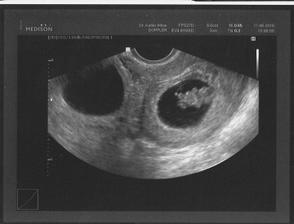

Jak rosteme s Aničkou v bříšku ;o)

Moc gratuluju a ŠŤASTNOU cestu až do cíle 😉 Dvě jsou lepší, než jedno 😉 😀

Petulko, VŮBEC se neboj!!! Všechno bude jak má!!! Naši miláčci se narodili 34+2 a už dávno předehnali své vrstevníky 😉!!!